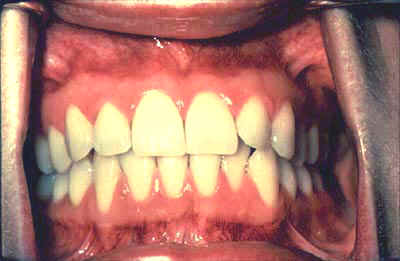

·         Pídale que muerda con las muelas, observe si hay oclusión  bilateral. Esta maniobra puede localizar algún tumor o quiste expansivo en la mandíbula, que altera la oclusión de ese lado.

Retracte la mucosa bucal. Examine primero la mucosa bucal derecha, luego la izquierda, extendiendo desde la comisura labial hasta el pilar anterior. Tenga en cuenta cualquier cambio en la pigmentación, color, textura, movilidad y otras anormalidades de la mucosa, asegurándose que las comisuras sean examinadas cuidadosamente y no sean cubiertas por los retractores durante la retracción de la mejilla.

Primero, examine  la cara bucal de la encía y los bordes alveolares (procesos) comenzando con la encía posterior derecha maxilar y el borde alveolar, y luego alrededor del arco del área posterior izquierda. Salte a la encía posterior mandibular izquierda y borde alveolar y muévase alrededor del arco del área posterior derecha.